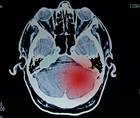

The Cell Death Pathway: Leveraging Glioblastoma Treatments

NeuroFrontiersThe Cell Death Pathway: Leveraging Glioblastoma Treatments

Diving into the Genetic Pathway: A Look at the STING Pathway & Brain Cancer

NeuroFrontiersDiving into the Genetic Pathway: A Look at the STING Pathway & Brain Cancer

Exploring New Research on Melanoma Brain Metastases

NeuroFrontiersExploring New Research on Melanoma Brain Metastases